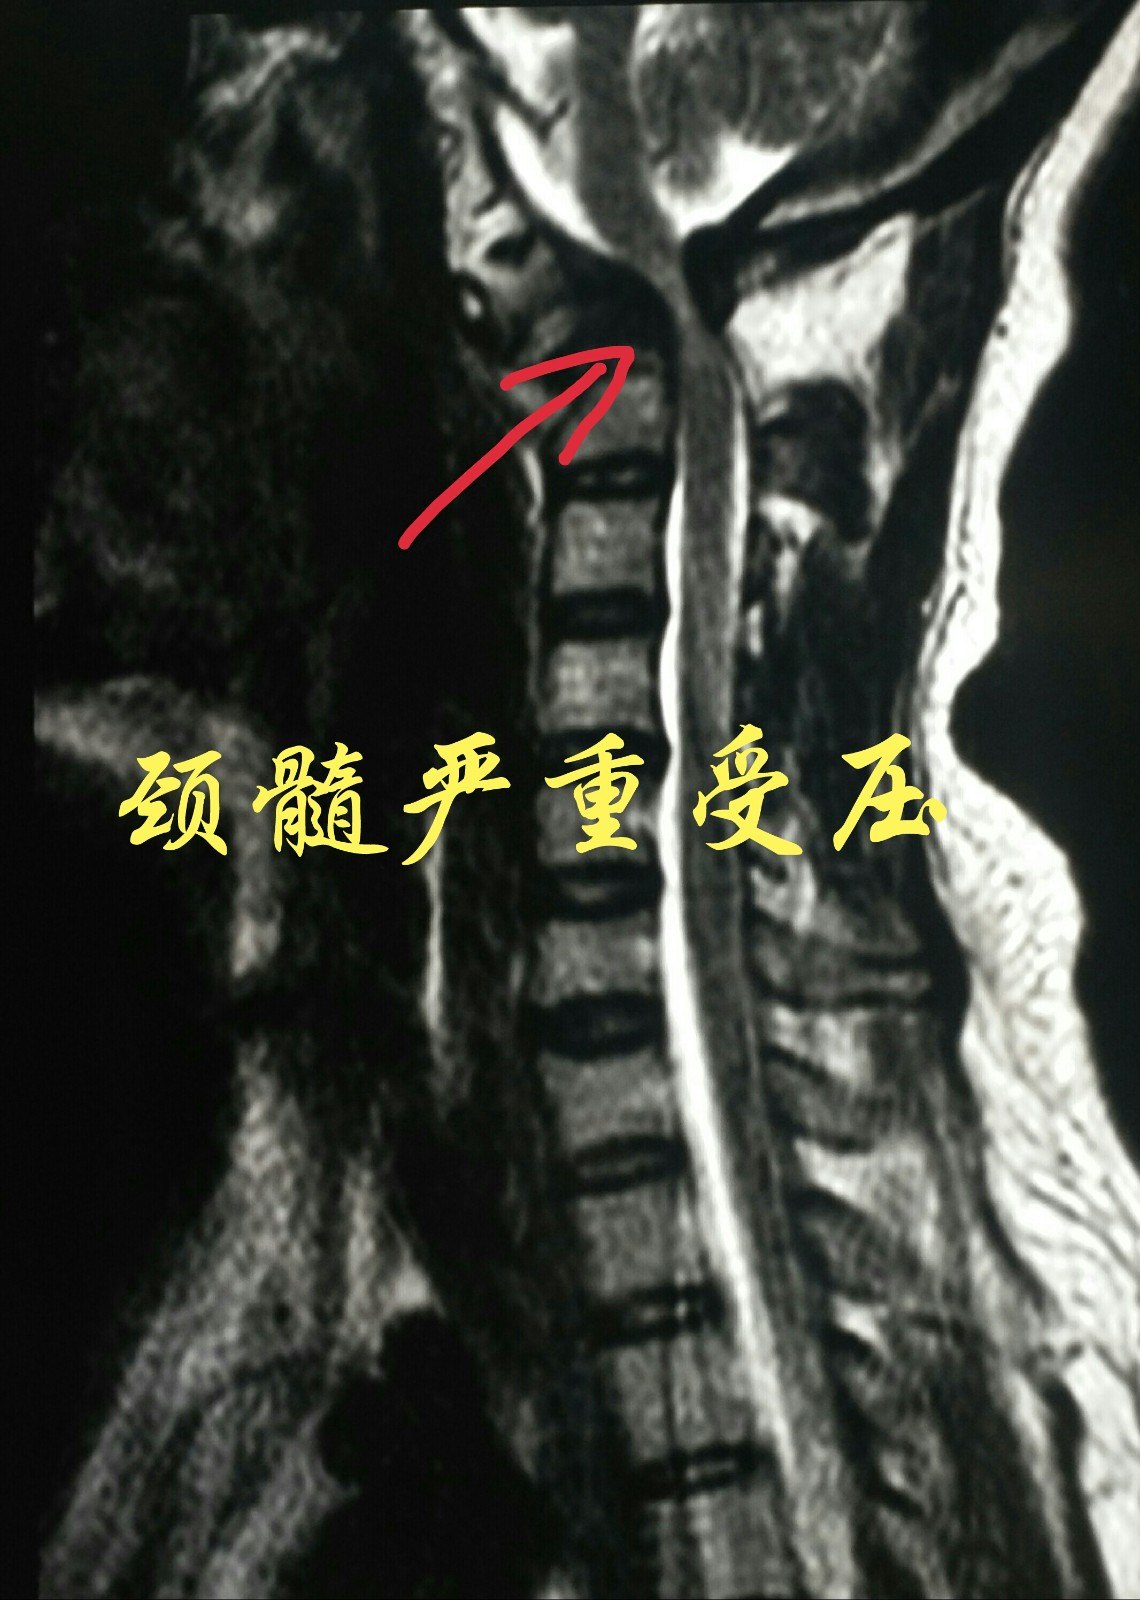

颈椎磁共振提示颅颈交界区脊髓严重受压

手术前